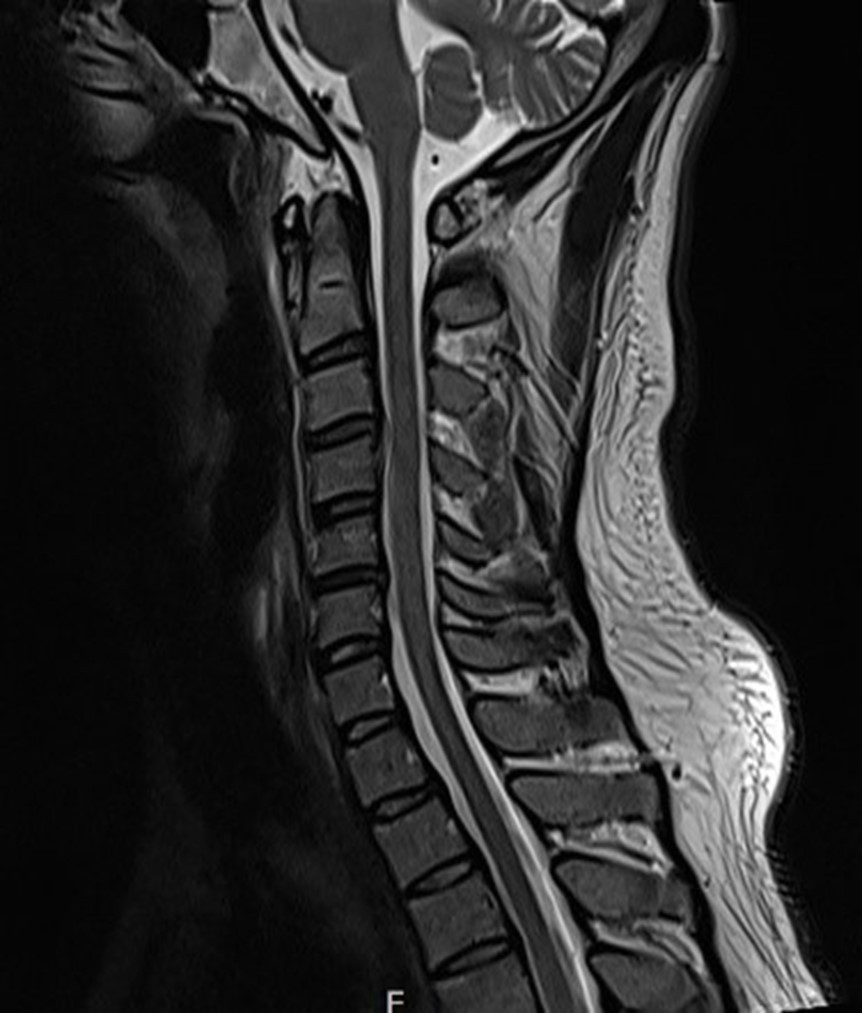

목 MRI 결과를 보니

역시 상부 경추에 문제가 있었어요.

디스크가 살짝 나와 있으면서

주변 근육들이 긴장되어 있는 상태였죠.

그림11.jpg 촬영 일시: 2025.05.09

<Fig 1. 디스크 소견의 목 MRI>

환자분께 설명해드렸어요.

목 디스크 때문에 주변 근육들이 긴장하고

이 긴장이 목에서 시작해서 머리까지 올라가면서

두통을 일으키고 있다고...

그리고 이 근육 긴장이 얼굴 근육에까지 영향을 줘서

눈떨림이 생긴 거라고 설명드렸어요.